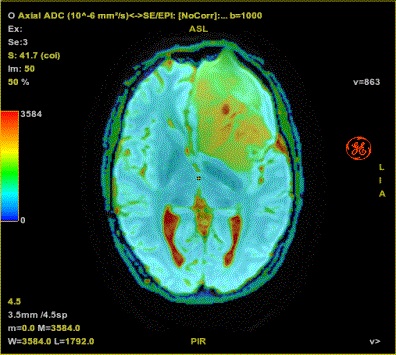

Figure 1. Example of ADC (10-6 mm2/s)